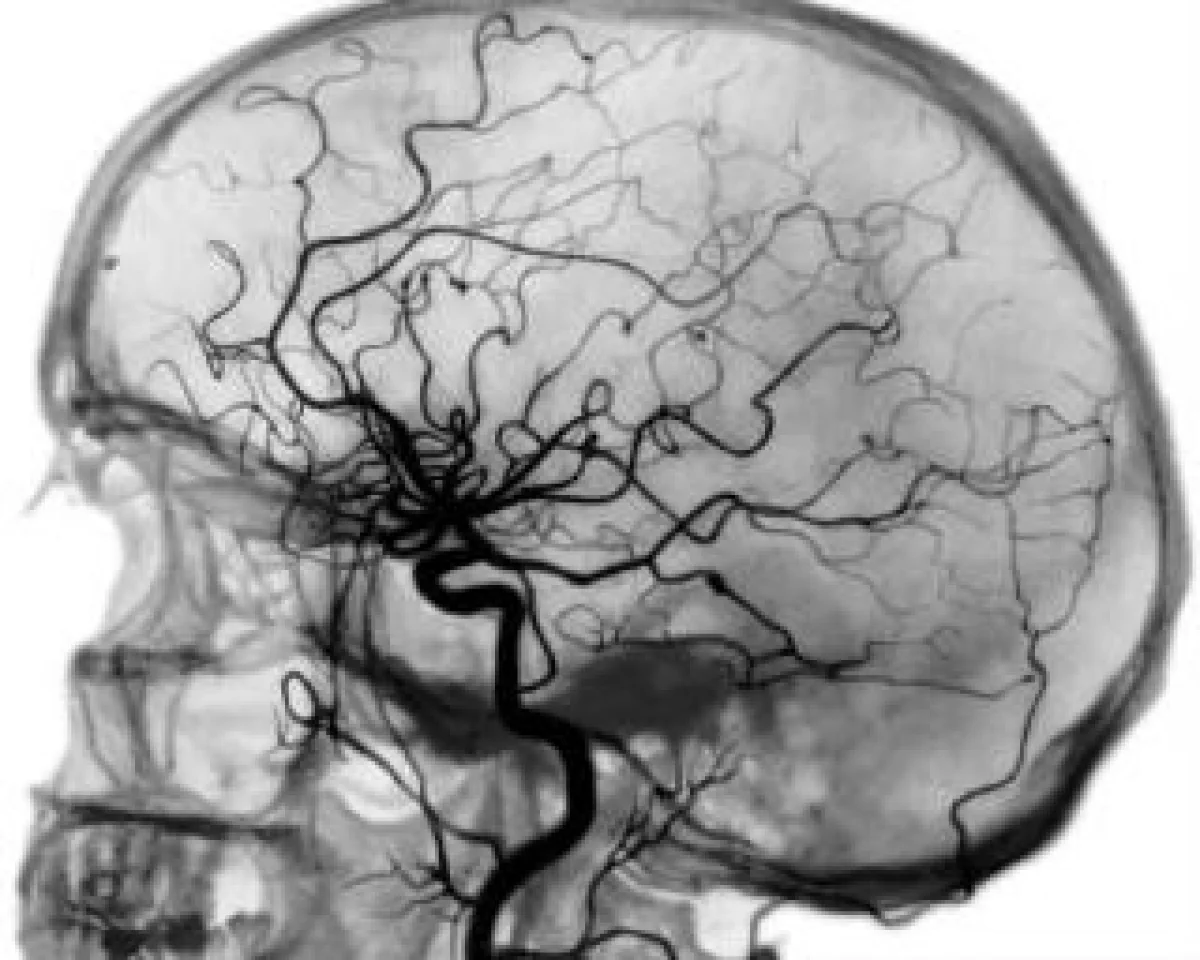

Ангиография сосудов головного мозга в деталях

Ангиография сосудов головного мозга используется представителями медицины довольно часто. Метод точный, безопасный и может похвастаться высоким порогом информативности. Примечательно, что с его помощью можно выявить патологии сосудов на ранних стадиях. Это серьезное преимущество. Кроме того, при помощи ангиографии возможна диагностика новообразований.

Какие задачи стоят перед МР ангиографией? Прежде всего, процедура позволяет в деталях рассмотреть разные функциональные или структурные изменения в области артерий, вен, а также капилляров, которые находятся в зоне головы. В этом случае можно легко определить степень стеноза и увидеть ширину просвета сосудов. Кроме того, процедура позволяет оценить активность кровотока, а также выявить многочисленные сопутствующие проблемы и патологии.

Ангиография сосудов головного мозга покажет сосудистые аневризмы и мальформации, различные изменения стенок сосудов, очаги инсультов или микроинсультов, различные посттравматические изменения, тромбозы синусов мозга, а также кисты, новообразования или гематомы. Обследование можно инициировать в одном из современных медицинских центров, к примеру, «Нейромед» в Киеве. В этом случае исследование будет проведено быстро и качественно. Диагностика проводится в оперативном порядке, исключая очереди и томительное ожидание. Пациенту лишь нужно прийти в центр в назначенное время. Результат будет готов в течение часа.